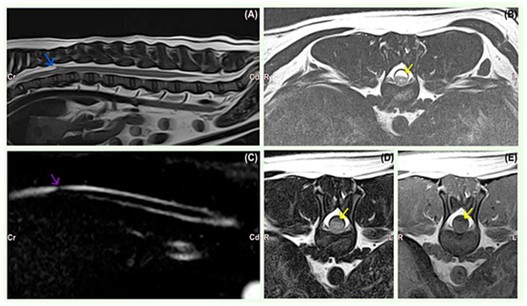

本研究回顾性分析了10例采用相同手术方案(椎板切除术联合硬膜切开,并使用非合成硬脑膜替代物Durepair)的SAD患犬,旨在描述其信号特征、病史、临床表现及影像学发现,并通过长期随访评估临床结局。

病例特征显示,法国斗牛犬(4例)和巴哥犬(3例)最为常见,提示遗传因素。病变部位与品种相关:罗威纳犬多见于颅颈段,小型犬多见于胸腰段(T7-L1)。典型MRI表现为蛛网膜下腔梭形扩张,部分病例并发椎间盘突出或椎体畸形。影像学检查在巴哥犬中还发现尾关节突发育不良。